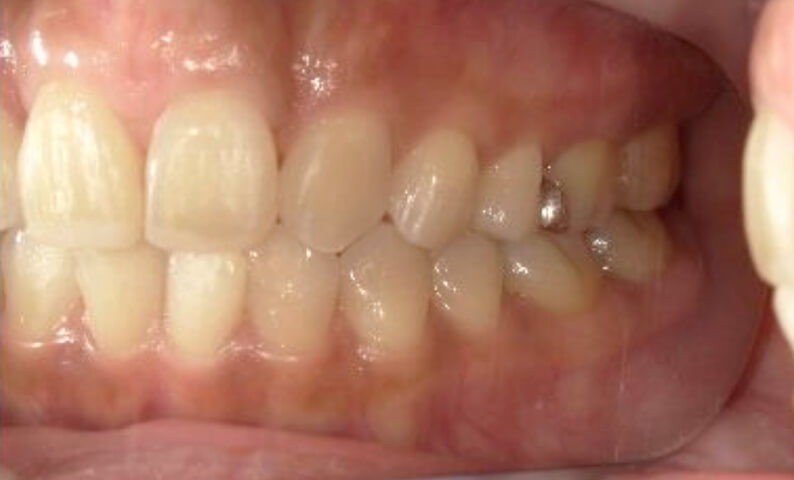

症例_003 下顎だけの部分矯正

治療期間:10ヶ月金額:24万円+税女性前歯のガタガタ下の前歯だけ上顎は補綴治療中

| Before | After |